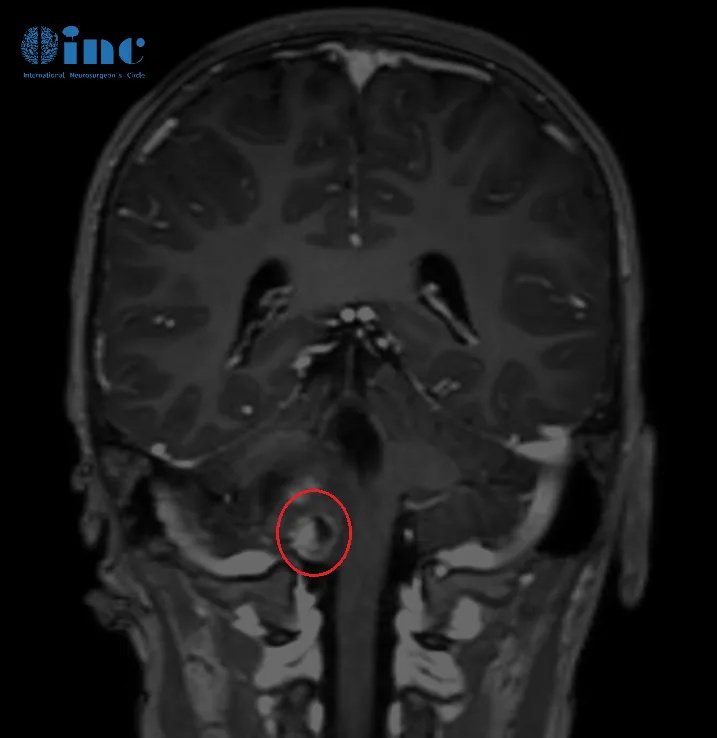

术前核磁影像

占位所处位置在人体的“生命中枢”脑干-延髓之上,延髓控制着人体的吞咽、呼吸等基本功能。

2022年08月25,常规核磁复查,结果提示肿瘤进展,延髓右部不规则肿胀范围约2.6cmX2.5cmX2.3cm。